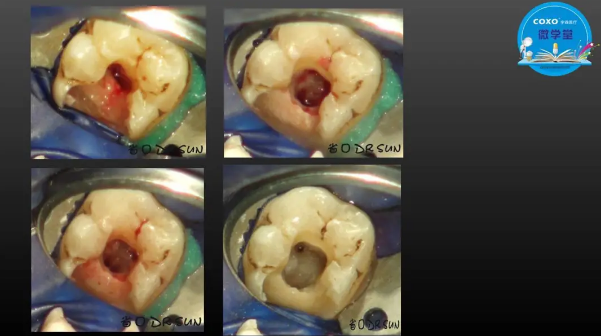

主講:孫書昱

主任醫(yī)師,牙體牙髓副主任, 廣東省口腔醫(yī)院牙體牙髓科 主任醫(yī)師。2003年碩士研究生畢業(yè),研究方向?yàn)檠荔w牙髓病學(xué),擅長(zhǎng)于牙體牙髓病的診斷、齲齒、牙髓炎、根尖周病的治療以及前牙美容修復(fù)。